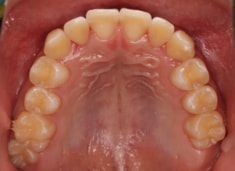

小児期ケース:反対咬合+上顎両側3番埋伏歯

(受け口+3番目の永久歯が左右両方とも埋まってしまい、はえてこない)

治療前